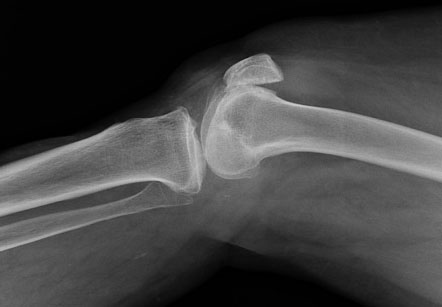

W zaawansowanym stadium tworzą się kostne wybrzuszenia. Powstają odchylenia osiowe, nieprawidłowe ustawienie nadmiernego wyprostu/zgięcia oraz widoczne deformacje. Utrudnia to wykonywanie czynności wymagających precyzyjnej motoryki (zapinanie guzików, otwieranie szklanek) i może znacznie ograniczać funkcjonalność dłoni.